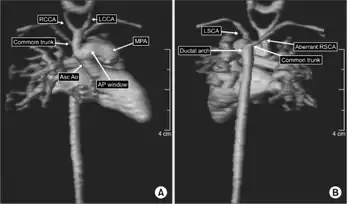

| a) Anterior and b) posterior views of cardiac magnetic resonance imaging depicting the interrupted aortic arch with an aortopulmonary window | |